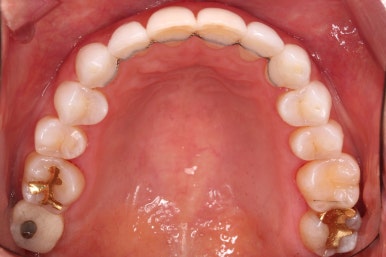

윗니에만 장치를 부착하고 부분교정을 시작했습니다.

환자분이 연산동부분교정 선택하신 장치는 엠파워 클리어라고 하는 자가결찰 세라믹 장치입니다.

장치 부착한 모습 참고해 주시고요.

적절하게 치간삭제를 일부 동반하여 빠른 시일 내에 가지런하게 해드리고 마무리를 했습니다.

환자분이 원하시는 만큼 가지런해졌고, 부가적으로 생길 수 있는 부분들도 수용 가능한 선에서 잘 마무리가 되었습니다.

3개월이라는 빠른 기간 내에(심미보철 보다 약간만 더 긴 시간) 치아의 손상없이 마무리를 잘 했습니다.